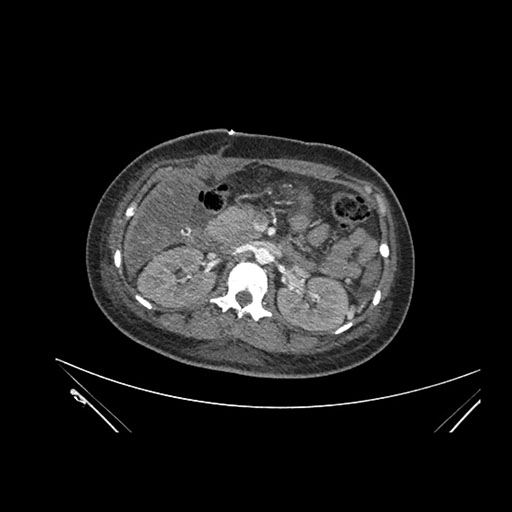

Imaging Analysis

Look through the patient's CT scan to identify any areas of concern for the necessary procedure.

Axial Arterial

Based on initial findings, which issue(s) would you be most concerned about?